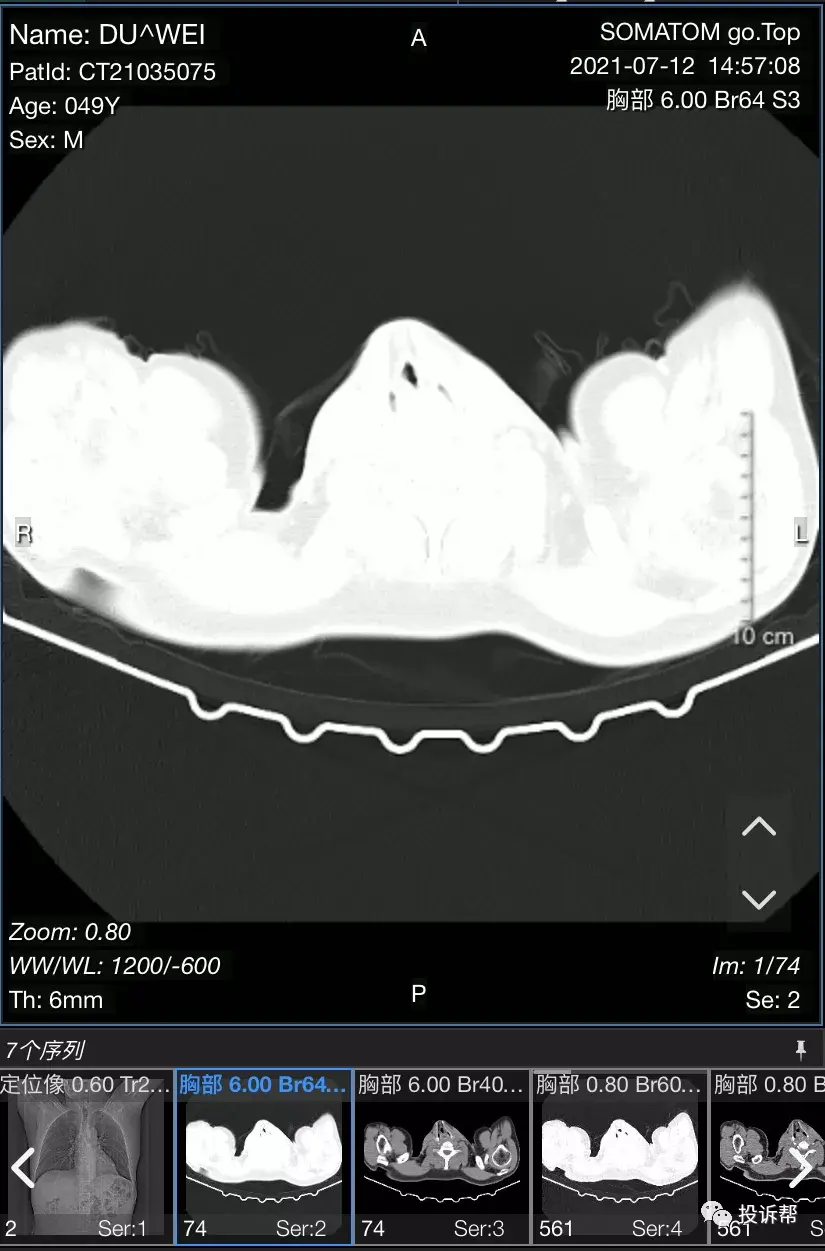

胸部ct解剖

解剖胸部丨胸部ct断层解剖图